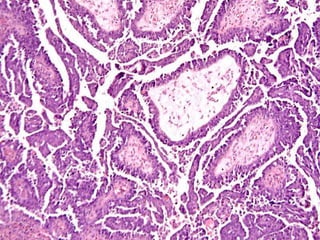

SEROUS, BENIGN

MUCINOUS, BENIGN

PSAMMOMA bodies are dried up papillae of papillary adenocarcinomas, usually in

the thyroid, but in ANY papillary adenocarcinoma